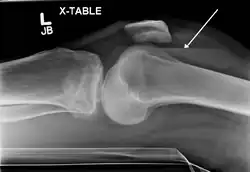

| Lipohemarthrosis (blood and fat in the joint space) seen in a person with a subtle tibial plateau fracture. The arrow indicates a fluid level between the upper fat component and the lower blood component. | |

X-ray of Hemarthrosis -

X-ray of Hemarthrosis